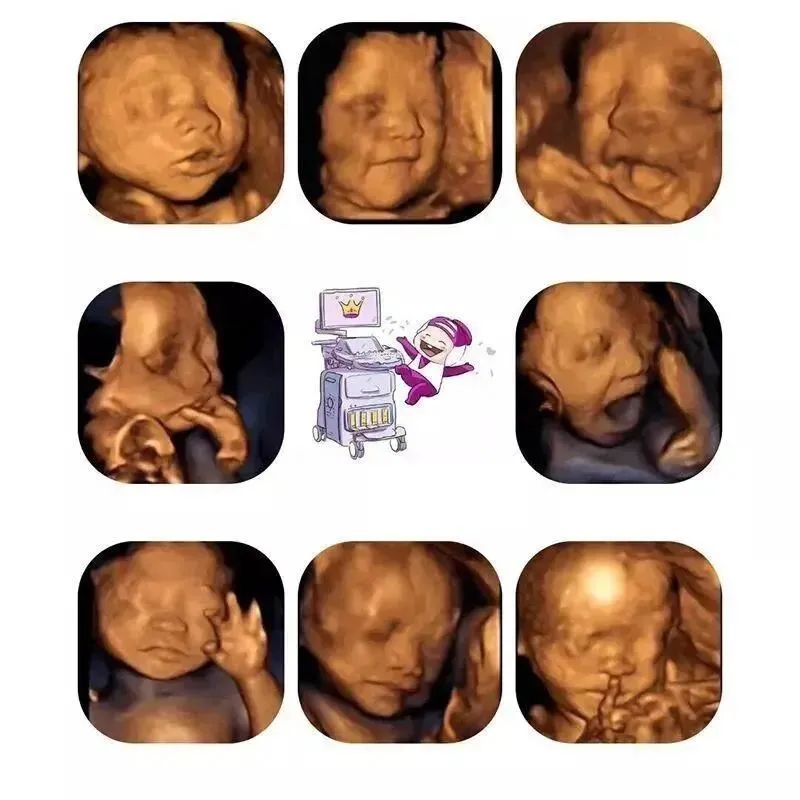

最后,这张图给到大家:艾玛妇产的胎儿系统超声主要包括中枢神经系统、颜面部、心脏、胸腔、腹壁、腹腔、四肢、常规胎儿评估等方面内容。

我们会通过四维技术把胎宝宝的活动状态和长相,做成图片和视频,免费赠送送给孕妈妈们,最后提醒宝妈们,做四维最重要的目的还是筛查宝宝的发育状况哦,咱们不要本末倒置了。